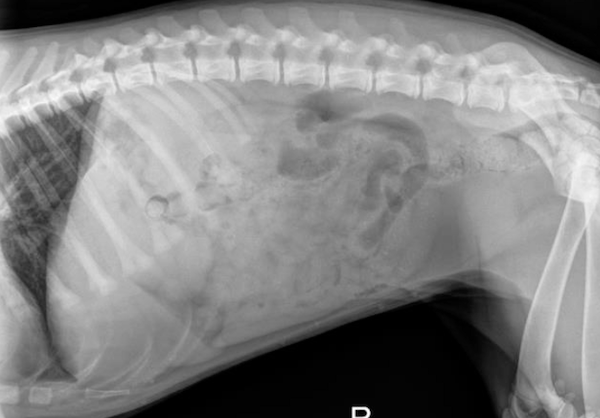

Radiograph findings:

The radiographs returned two radiopaque foreign materials in the stomach (shown above by the red arrows). These objects were suspected to be rocks. In order to confirm the location of these objects two views were taken including the lateral views above as well as a ventrodorsal (VD) view (not pictured).

Treatment